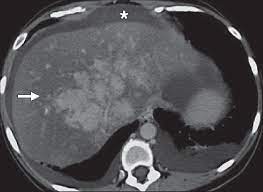

Chiasmata -mə-tə or chiasmas also chiasms 1. Esophageal varices are extremely dilated sub-mucosal veins in the lower third of the esophagus. Located in metro Denver northern Colorado and western Nebraska serving all of the Front Range our team consists of board-certified and fellowship-trained interventional radiologists. This results in hepatic congestion similar to Budd-Chiari syndrome and post-sinusoidal portal hypertension. The patients condition should be monitored throughout the procedure. They are most often a consequence of portal hypertension commonly due to cirrhosis. Toxic injury to liver sinusoids causes sloughing of endothelial cells that embolize to hepatic venules and cause eventual fibrosis of the venules. Coin in the Esophagus. There is no clear consensus regarding the number of occluded veins some authors claim that there should be at least one occluded hepatic vein 7 others state that there are no significant.

Carcinoma of the Colon. Budd-Chiari syndrome a blockage in one or more veins that carry blood from the liver back to the heart. And coumarin skin necrosis adrenal gland hemorrhage and infarction. Toxic injury to liver sinusoids causes sloughing of endothelial cells that embolize to hepatic venules and cause eventual fibrosis of the venules. Chiari malformation CM is a structural defect in the cerebellum characterized by a downward displacement of one or both cerebellar tonsils through the foramen magnum the opening at the base of the skull. Embolism and thrombosis of. La présence dune ou plusieurs affections prothrombotiques est fréquente La prise en charge repose sur un traitement anticoagulant précoce le traitement de l.